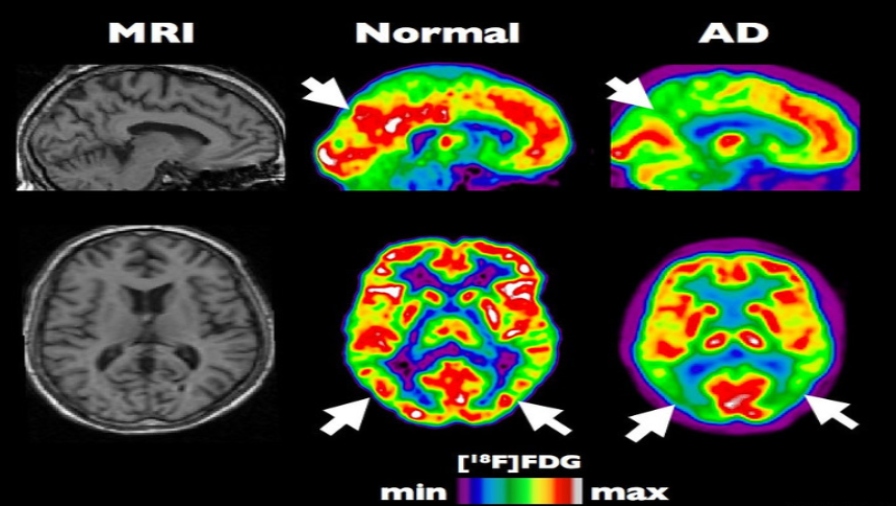

Images of brains with and without Alzheimer's Disease, with MRI on the left and PET the middle and right scans. Photo: Institut Douglas

Within the network are 10 clinics offering positron emission tomography (PET) scanning, a technique commonly used in oncology and, together with MRIs and CTs, can show a more detailed picture of a body’s functioning, especially at a cellular level.

Qscan’s current business model sees it provide a complete infrastructure and services platform for radiologists, sonographers and support staff, who can concentrate on patient care.